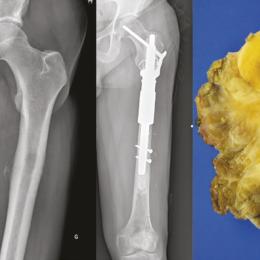

Hygroma dans un contexte d’amputation bilatérale des membres inférieurs

Une enfant de 11 ans est amputée des membres inférieurs à la suite d’un choc toxique survenu dans le contexte d’une...